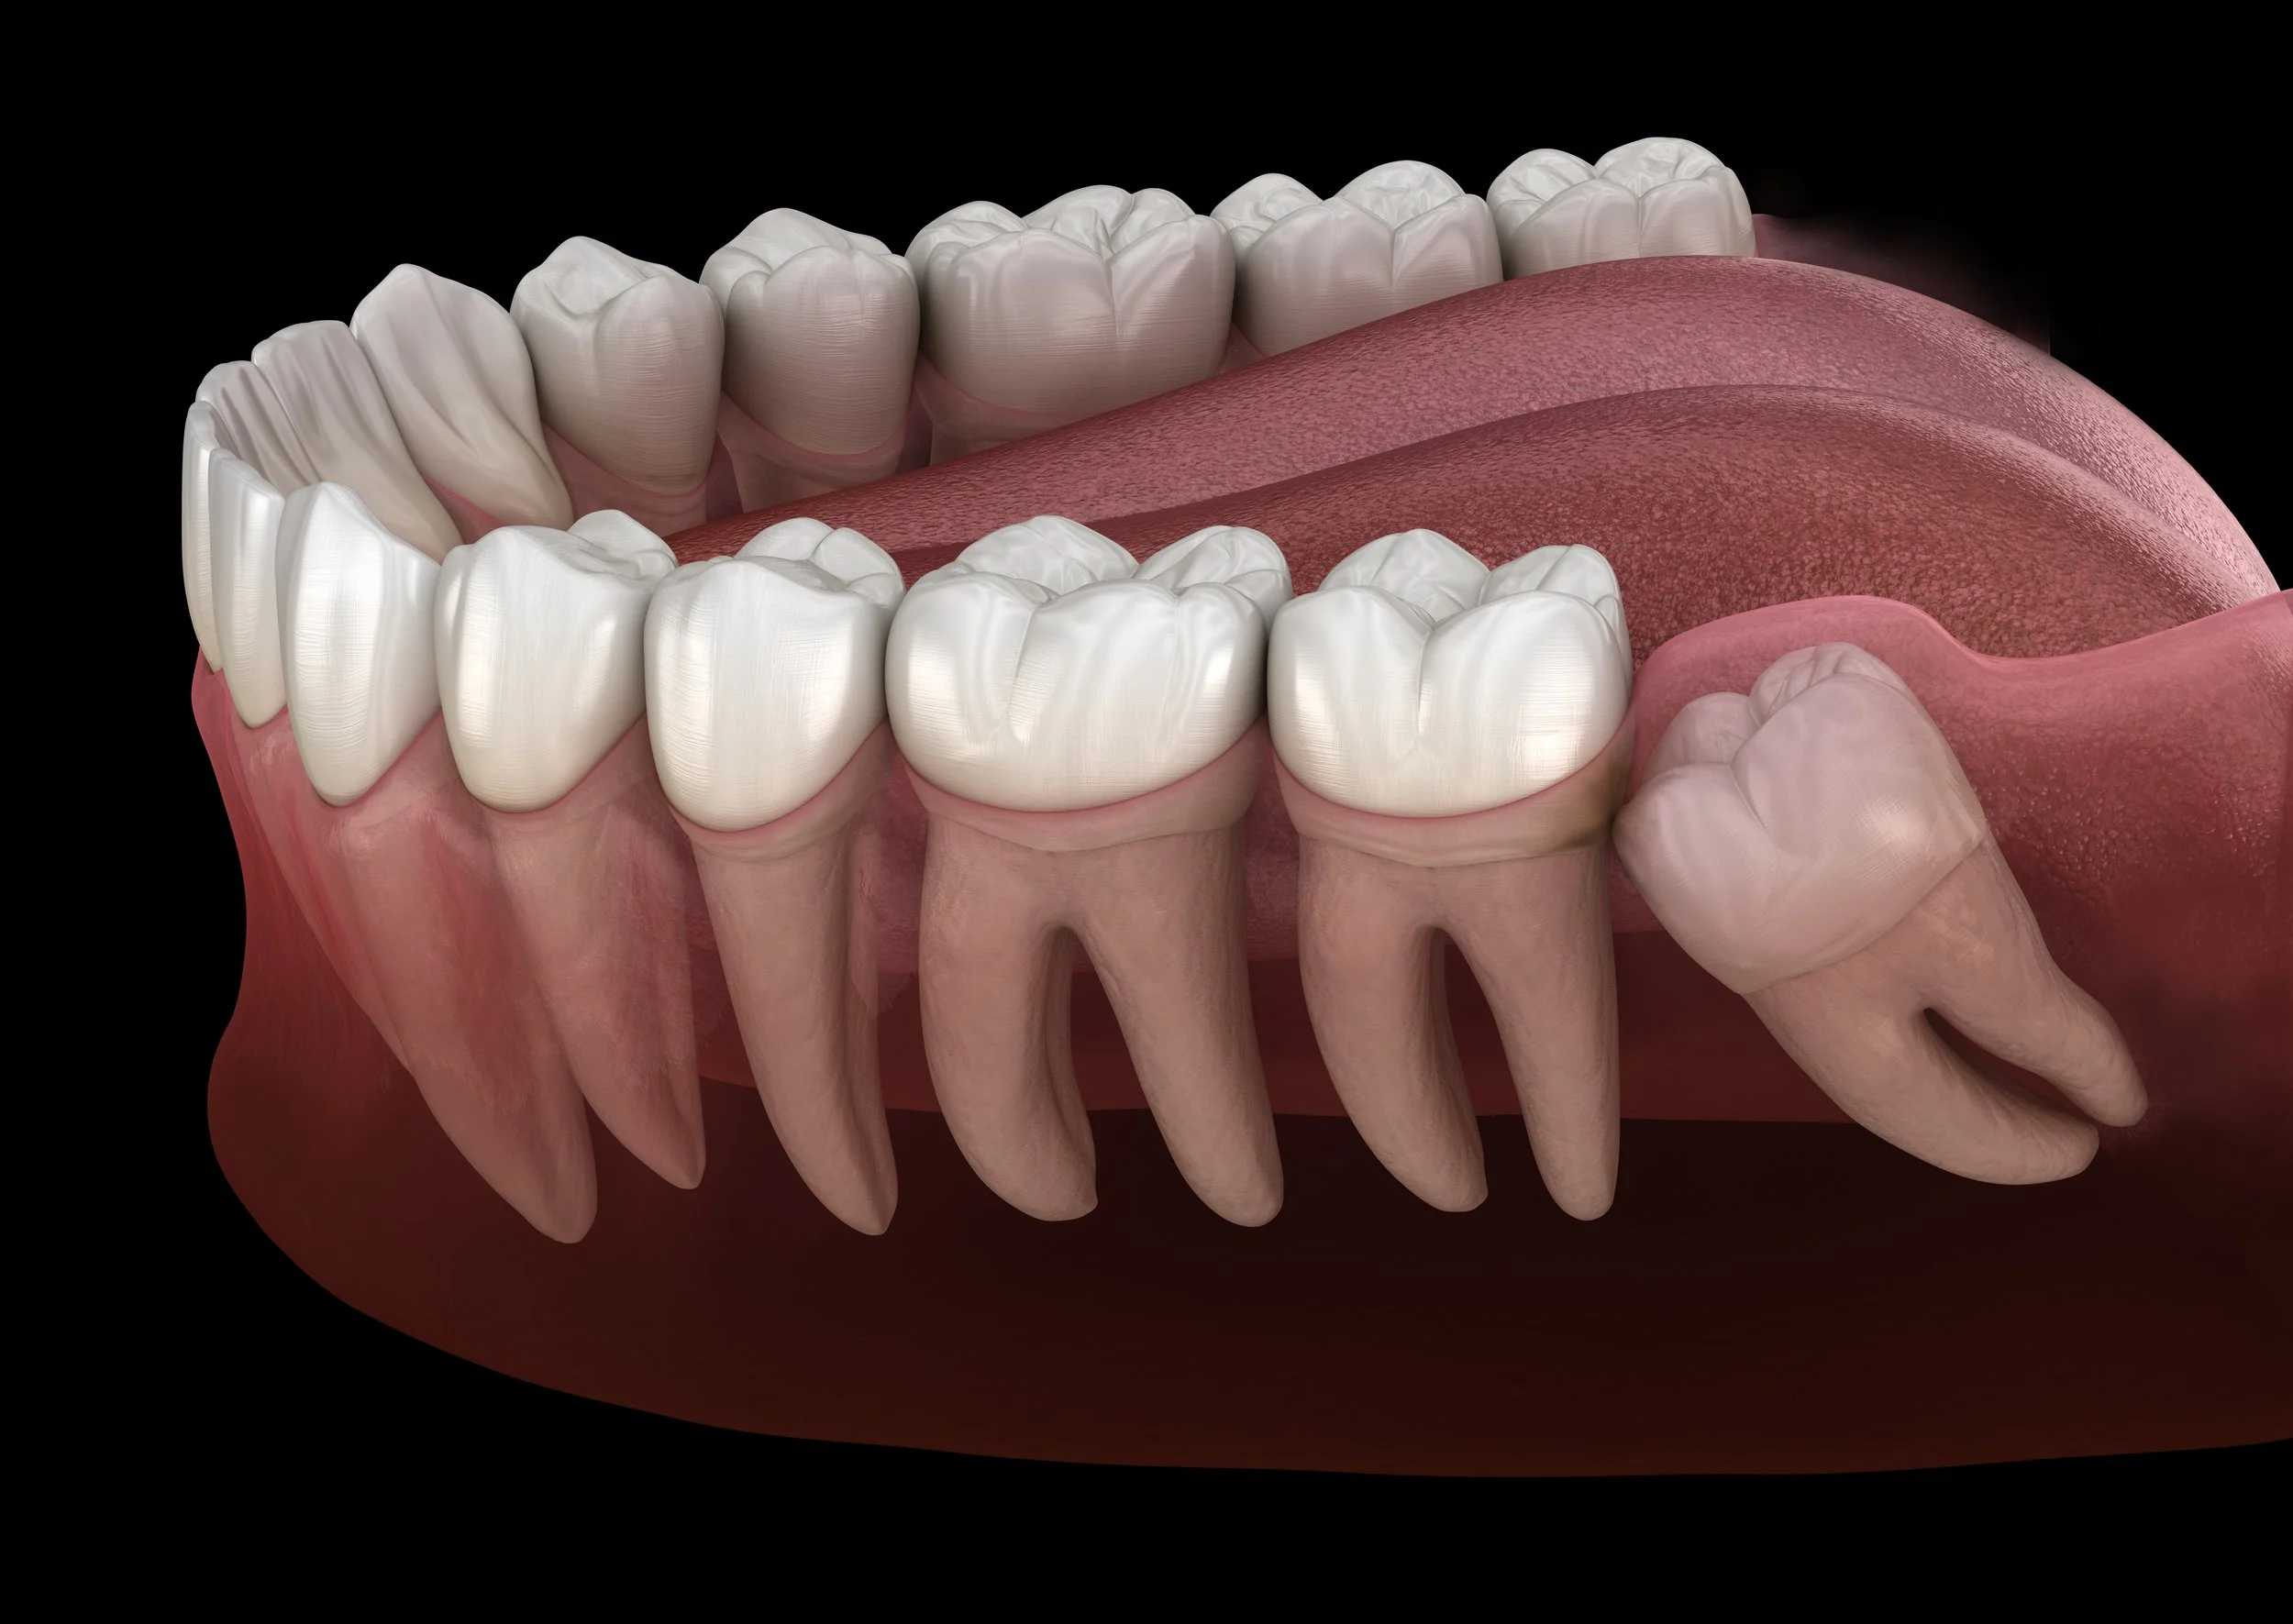

The Procedure: What to Expect

Consultation & Planning: Comprehensive evaluation of your teeth and medical history.

Extraction & Suturing: Teeth are removed efficiently, and sutures are placed to promote faster healing.